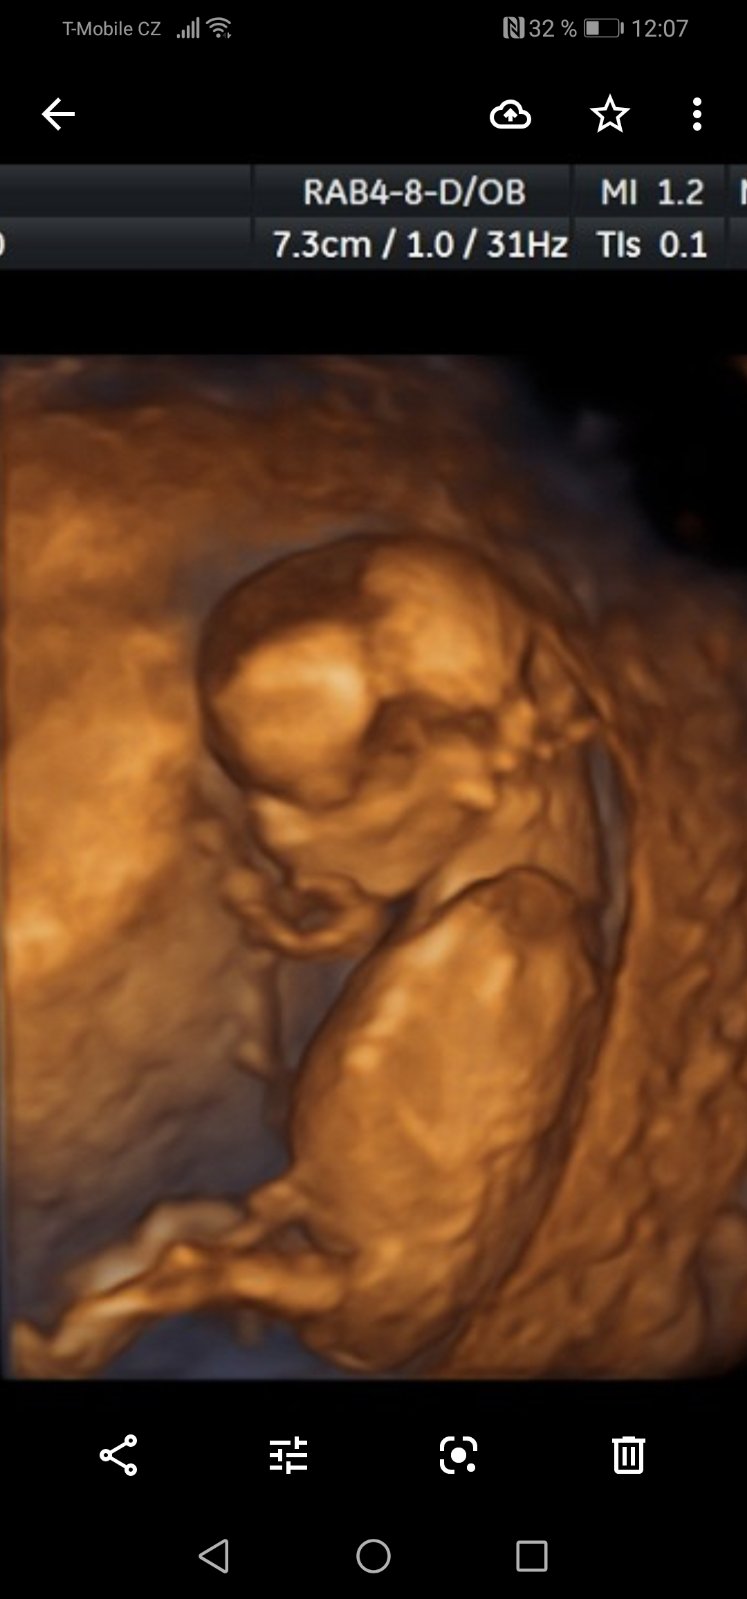

Ahoj maminky a budoucí maminky 😉 Prosím, poradila byste mi některá, co vidíte na fotce z ultrazvuku ve 20. týdnu za pohlaví? Určitě jste foteček viděly už mraky, proto vás žádám o radu...Nechci nikoho ovlivnit, proto svůj tip řeknu později 🙂 Děkuju moc!!!

@sebinka123 řekla bych holka, jinou fotku nemáte? Leží tam trochu nakřivo 🙂

@kajda3 mám ještě tyhle. Ta jedna jsou vyloženě nožičky a bříško, je jakoby cele k nám.

@kajda3 ještě možná tuhle, tady přirození trochu je vidět, po přiblížení. Prý ty pysky jsou taky hodně velké. Prostě nevím. 😥